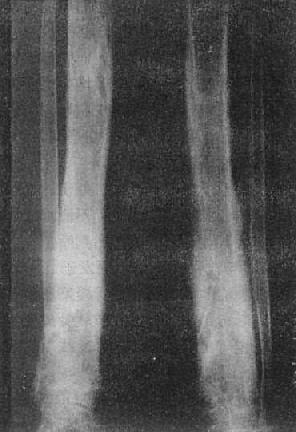

图2-1-12 胫骨慢性化脓性骨髓炎,花边状骨膜增生

图2-1-13 胫骨慢性化脓性骨髓炎

上图可见骨破坏及骨膜反应,有死骨形成。下图为半年后,死骨更为明显

2.慢性化脓性骨髓炎 是急性化脓性骨髓炎未得到及时而充分治疗的结果。临床可见排脓瘘管经久不愈或时愈时发,主要是因为脓腔或死骨的存在。X线片可见到明显的修复,即在骨破坏周围有骨质增生硬化现象。骨膜的新生骨增厚,并同骨皮质融合,呈分层状,外缘呈花边状。因此,骨干增粗,轮廓不整,骨内膜也增生,致使骨密度明显增高,甚至使骨髓腔闭塞。虽然有骨质修复、增生,但如未痊愈,则仍可见骨质破坏和死骨(图2-1-13)。因有骨硬化,常需用过度曝光片或体层摄影才能显示。